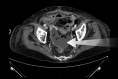

Results: Five patients (2 male, age 44-89 years) were included. Four patients had postoperative PFCs, and 1 presented with a pelvic abscess complicating acute diverticulitis. Two of 5 had fecal diversion; the remaining 3 had unaltered large-bowel anatomy. One case had a concomitant abdominal collection, treated with percutaneous drainage in the same session. An electrocautery-enhanced LAMS delivery system (15 × 10 mm) was used in all cases. EUS-TRD was performed with the direct-puncture technique and lasted less than 10 minutes in 4 cases; in the remaining case, needle puncture and LAMS placement over a guidewire was required, and the procedure length was 14 minutes. The clinical success rate was 100%. LAMSs were removed after a median of 14 (range, 12-24) days. One patient reported partial proximal LAMS migration after 24 days (mild adverse event). No PFC recurrence was observed.